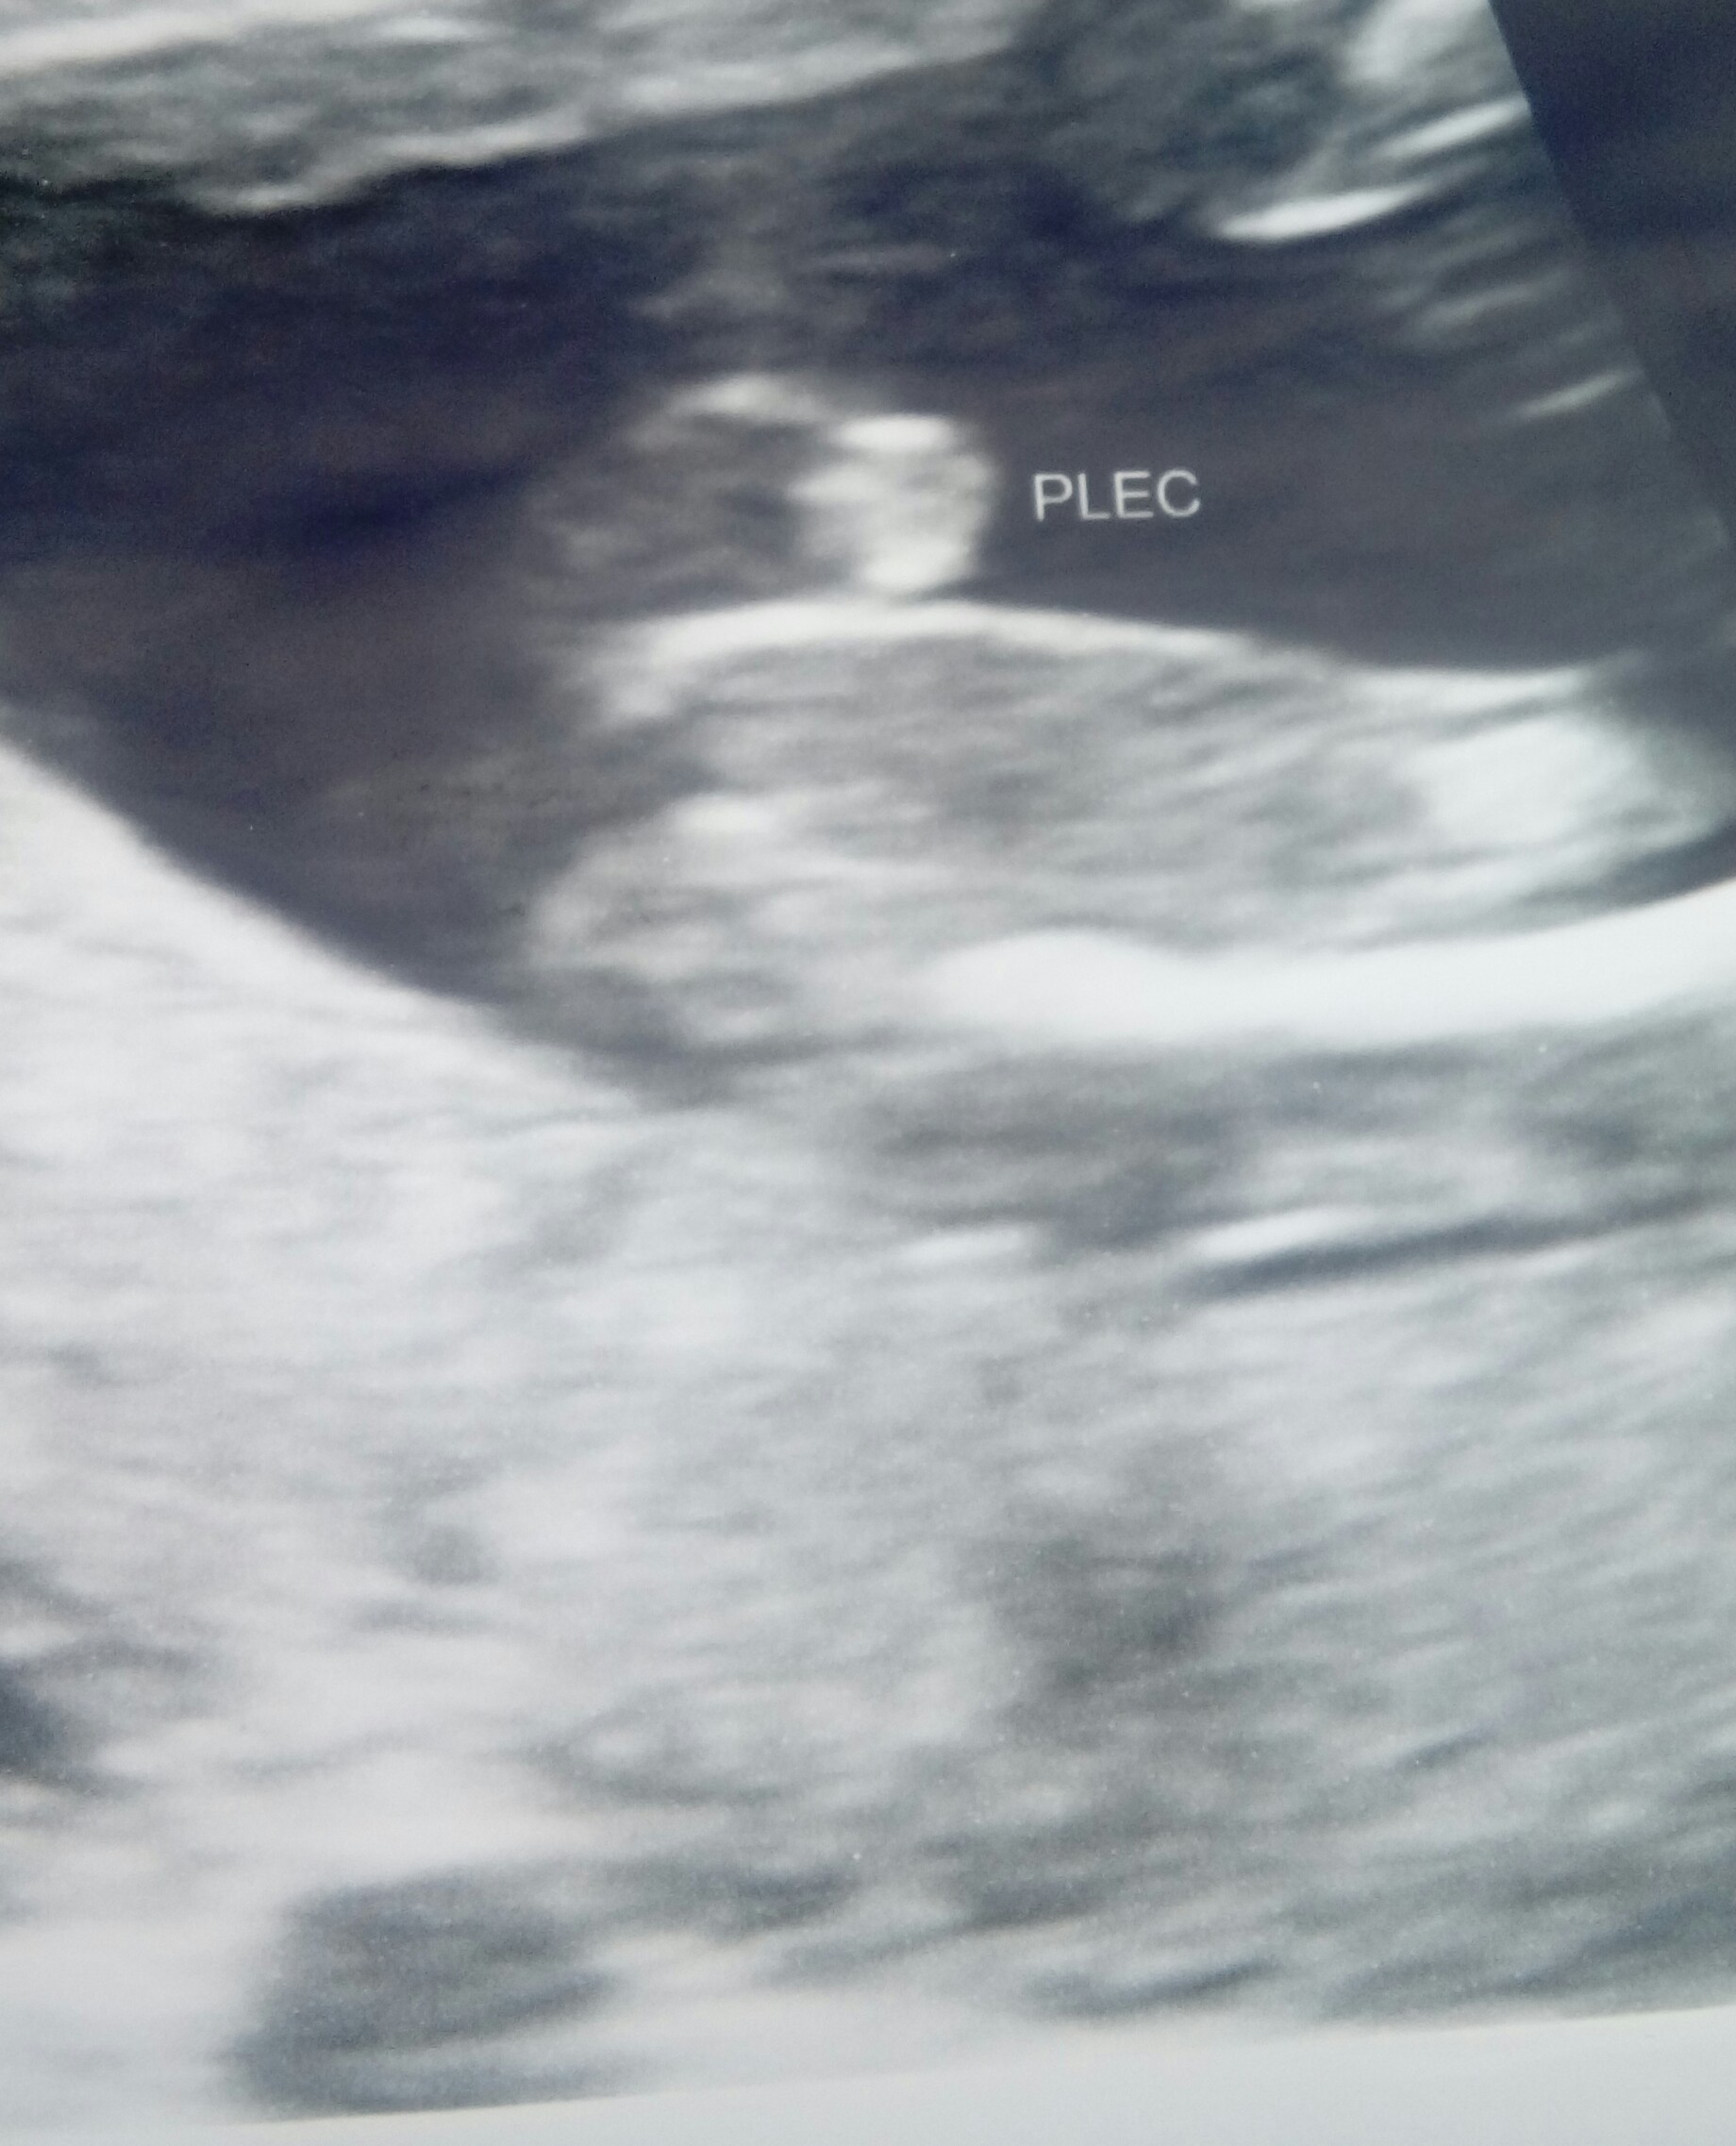

Bylam dzis na wizycie i mam zdjecie siusiaka!:D no i dorzucam brzuchol:) to u mojej mamy wiec nie mam swoich ukochanych kapci flamingow;)

Załączniki

• 20180628_085911-1.jpg

20180628_085911-1.jpg

475,2 KB · Wyświetleń: 127